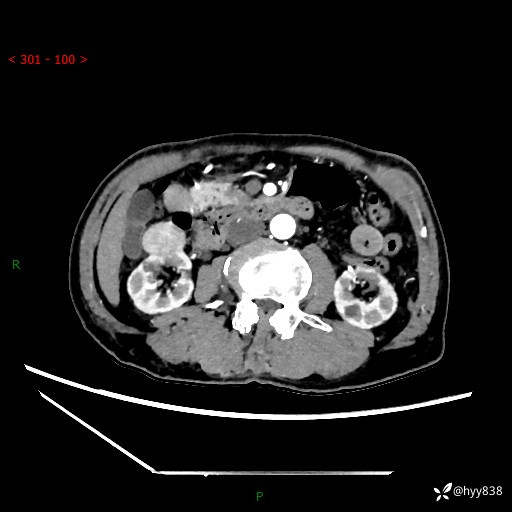

辅助检查:CT

肾脏CT平扫

增强(皮质期+髓质期+排泄期)

三期CT值:132hu 107hu 81hu